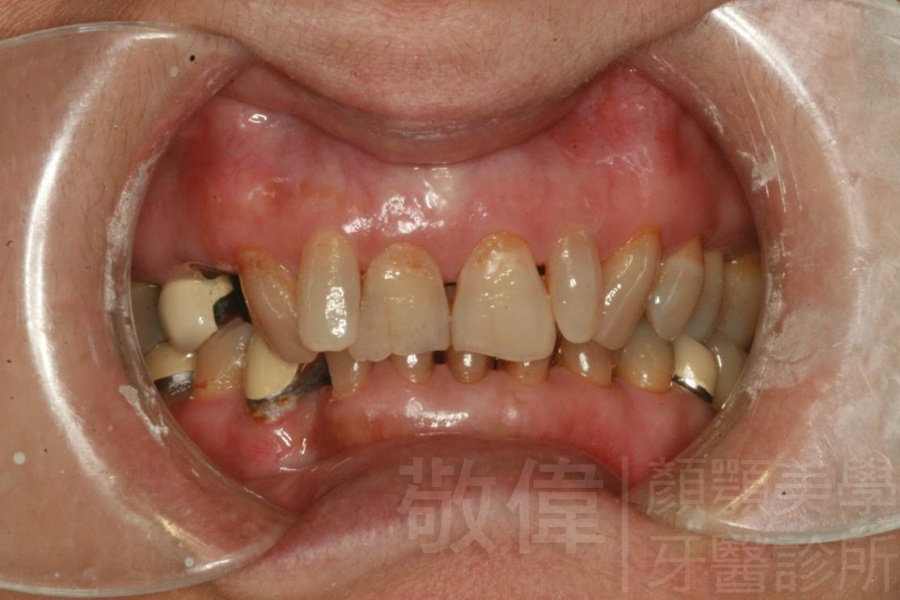

| 8 | 前牙美容 | 快速矯正之美容晶瓷貼片及晶鑽瓷冠 | ||